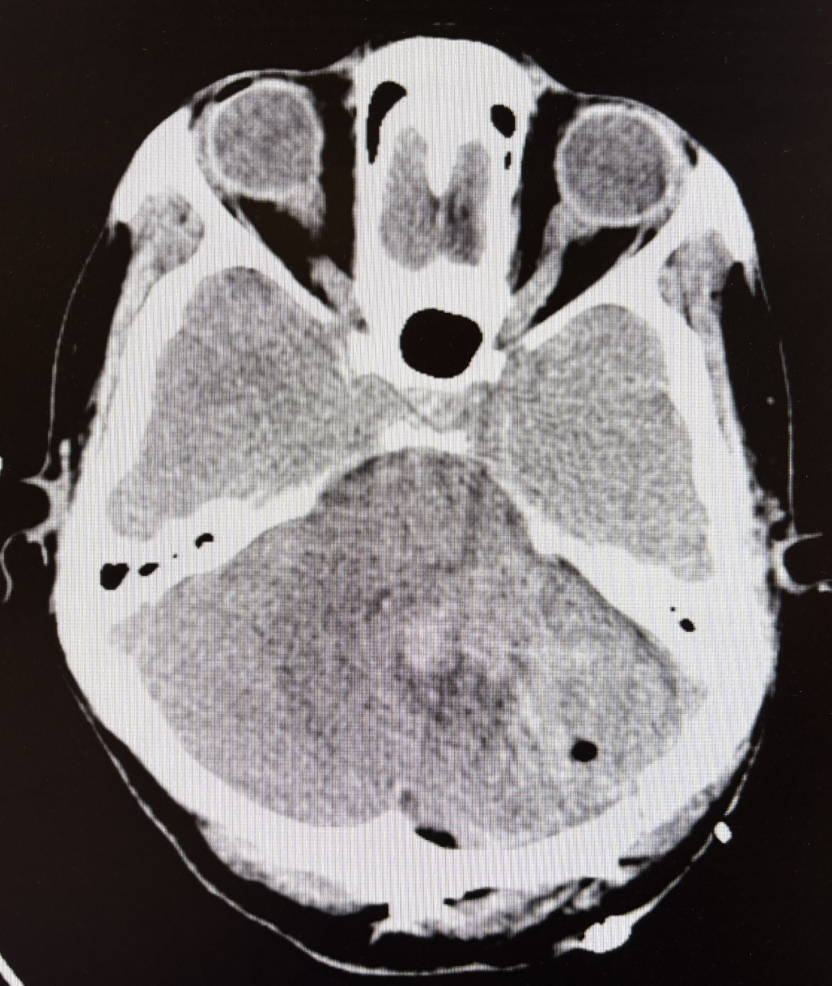

1期术前CT示:小脑出血

1期术后CT